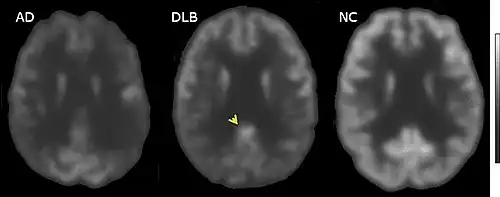

FDG-PET horizontal cross section of brain, with brighter areas indicating higher metabolism. The cingulate island sign is indicated by the arrowhead.

FDG-PET of brain surface, with the color red indicating areas of high metabolism. The occipital lobe in DLB (arrows) shows less activity than in AD.

PET or SPECT imaging can be used to detect reduced dopamine transporter uptake and distinguish AD from DLB.[56][144] Severe atrophy of the hippocampus is more typical of AD than DLB.[145] Before dementia develops (during the mild cognitive impairment phase), MRI scans show normal hippocampal volume. After dementia develops, MRI shows more atrophy among individuals with AD, and a slower reduction in volume over time among people with DLB than those with AD.[32] Compared to people with AD, FDG-PET brain scans in people with DLB often show a cingulate island sign.[32]